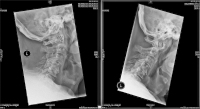

Abbildung 5: Seitliche Funktionsaufnahmen einer atlanto-axialen Instabilität. Die Hilfslinien zeigen die Veränderung des atlanto-dentalen Intervalls in Flexions- und Extensionsstellung.

Keywords: atlanto-axiale InstabilitätExtensionsstellungFlexionsstellungFunktionsaufnahmeHWS